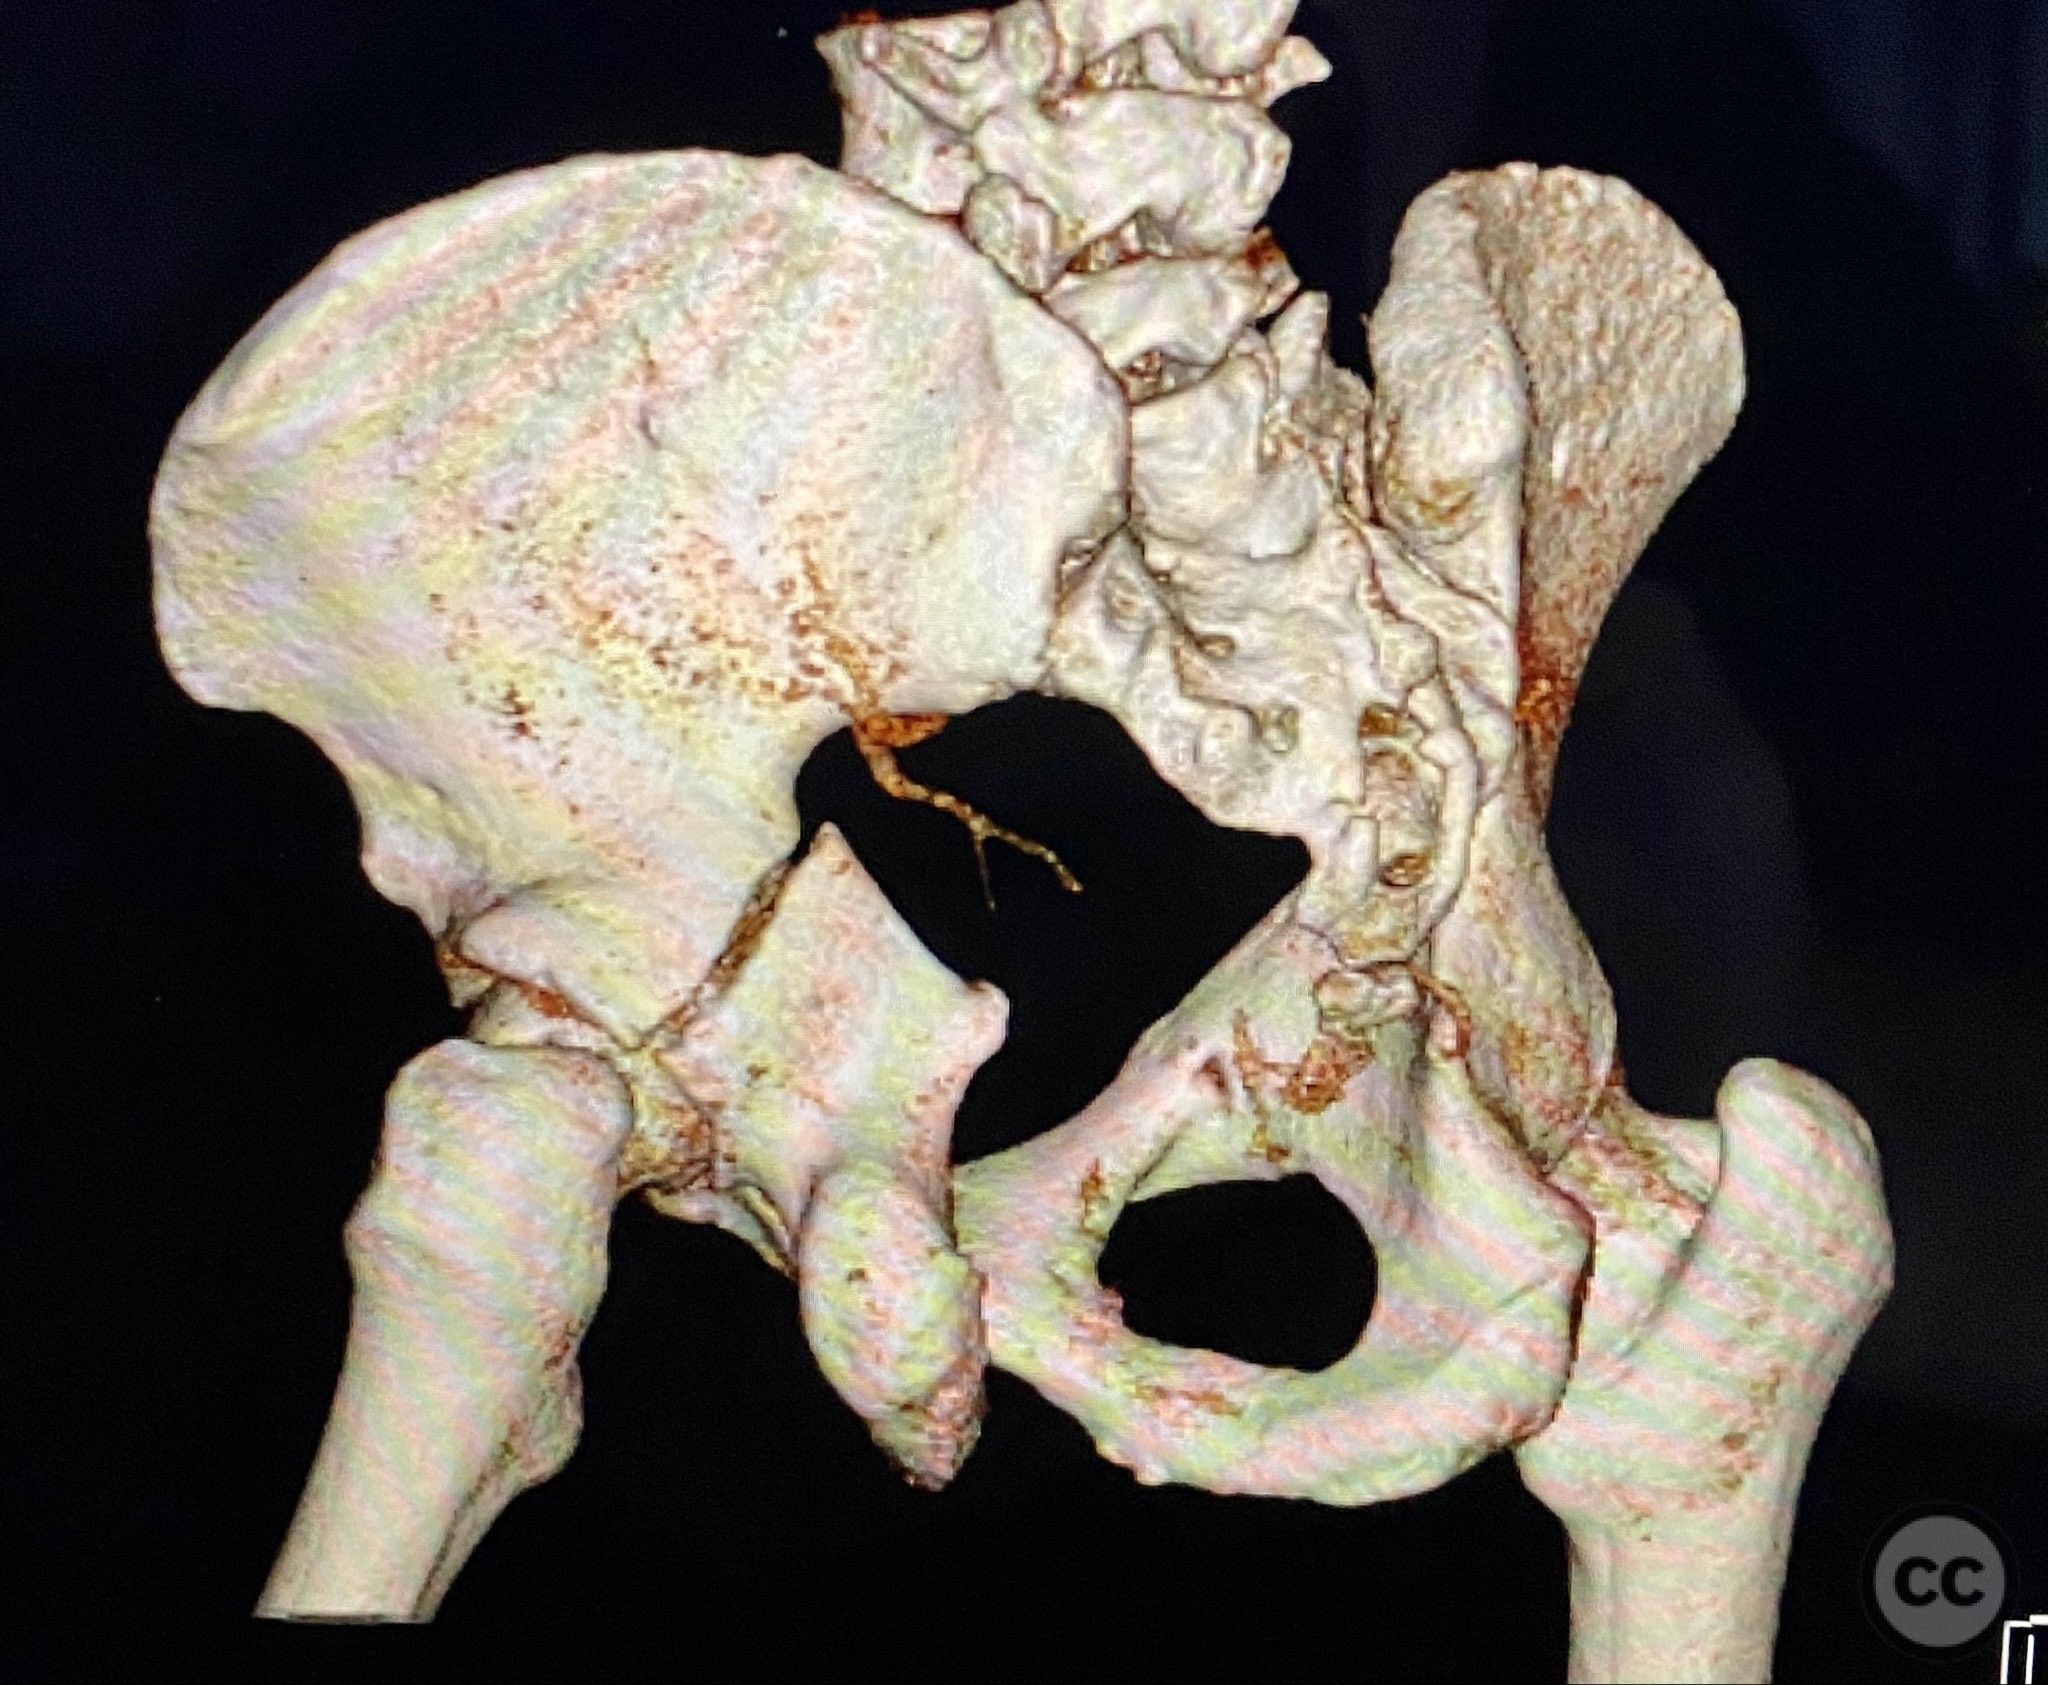

Clinical and radiological findings:  Adult male with a closed, comminuted left femoral shaft fracture and complex pelvic ring injury. Initial imaging demonstrated bilateral sacroiliac (SI) joint disruptions and a left-sided transtectal transverse acetabular fracture (Letournel-Judet: transverse type), with the fracture line exiting through the posterior wall region but without a discrete posterior wall fragment. The femoral head was displaced caudally, following the unstable distal acetabular segment, resulting in loss of congruency with the intact acetabular dome. There was also a symphyseal disruption. No associated abdominal, visceral, thoracic, cranial, or other injuries were present. Application of a circumferential pelvic binder resulted in visible changes in pelvic alignment on imaging. AO/OTA Classification: - Pelvic ring: 61-C1.3 (bilateral SI joint disruption, complete instability) - Acetabulum: 62-B1 (transverse fracture) - Femur: 32-C3 (comminuted diaphyseal fracture)

Initial reduction of the posterior column was attempted using a Jungbluth clamp; however, intraoperative fluoroscopy revealed suboptimal reduction despite satisfactory direct visualization. A perpendicular reduction clamp was then applied, resulting in improved alignment as confirmed by fluoroscopy. The transverse acetabular fracture was stabilized with two 4.5 mm cortical screws placed across the fracture line, followed by application of posterior column plates for additional stability. The symphyseal disruption was managed non-operatively without direct stabilization.

Orthopaedic implants used:   - Anterior two-pin external fixator - Percutaneous iliosacral screw(s) - Percutaneous transsacral screw(s) - Intramedullary femoral nail - 4.5 mm cortical screws (acetabular fixation) - Posterior column reconstruction plate(s)